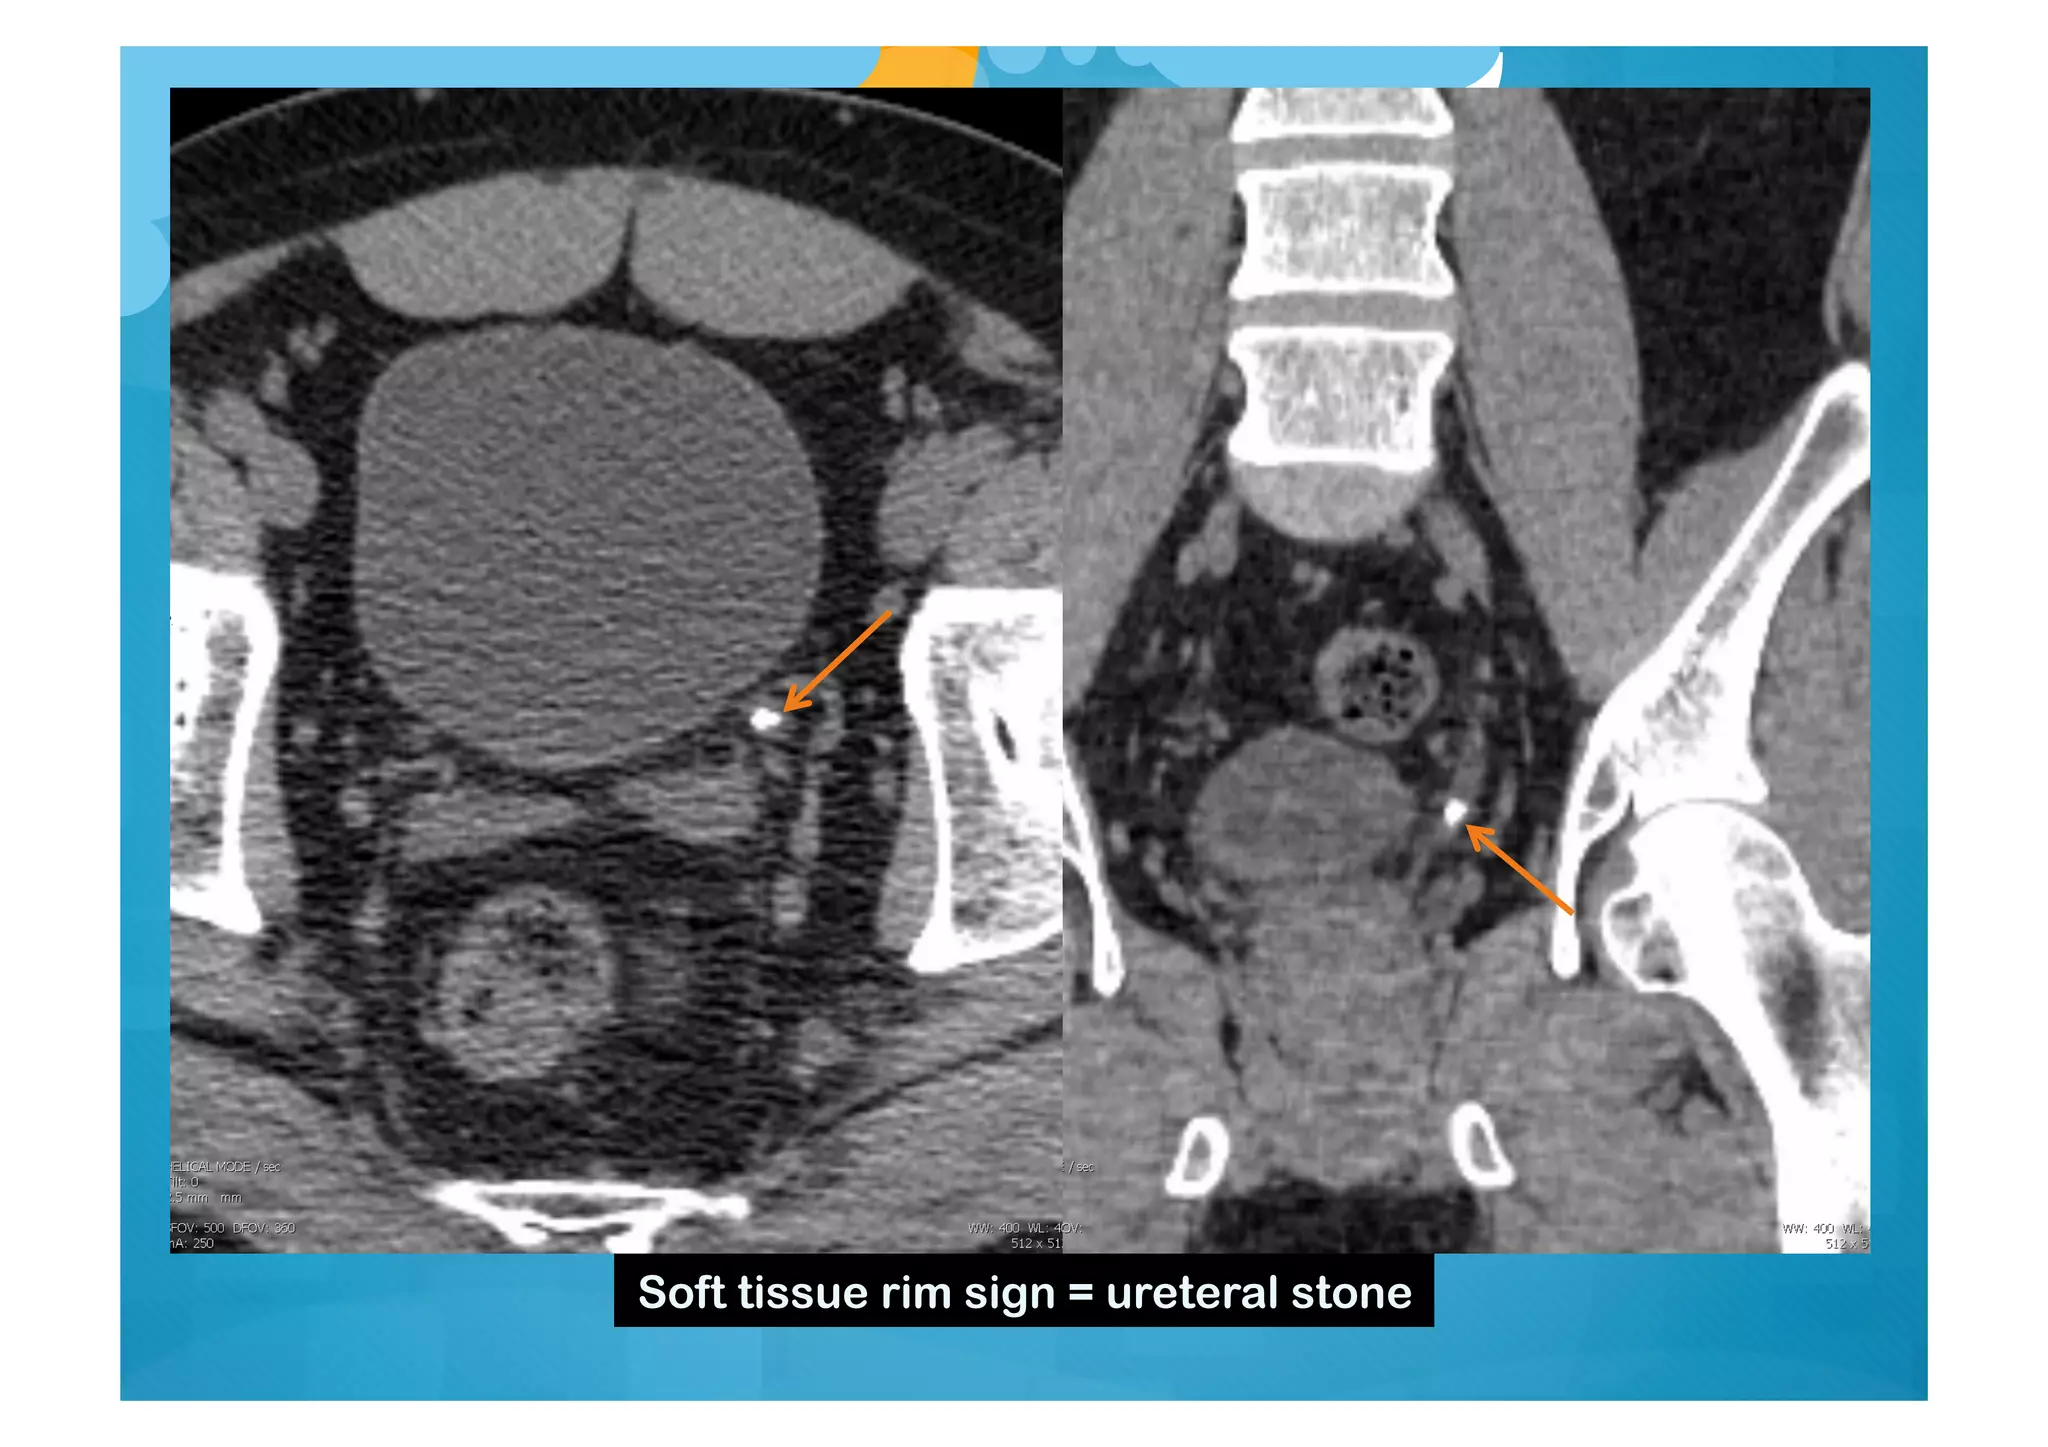

Soft tissue rim sign = ureteral stone

Soft tissue rimsign = ureteral stone